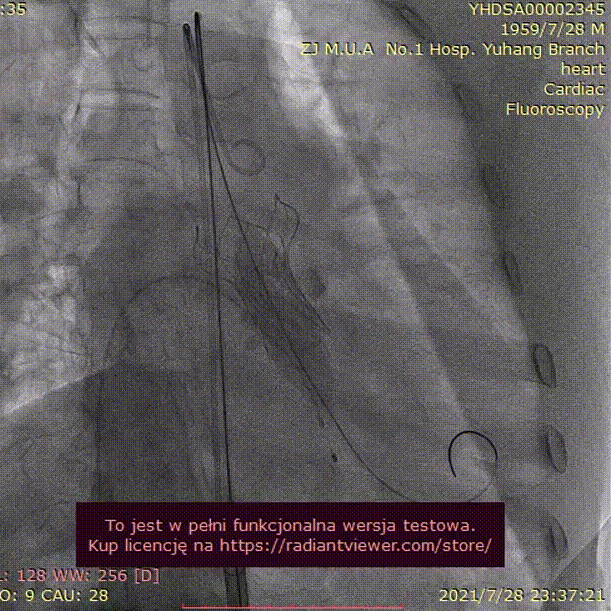

手术过程:

20mm球囊预扩

(无腰征,少量瓣周漏)

TAV24 瓣膜释放前定位

释放过程

植入后造影

术后压差1mmHg

术后结果:测左室-主动脉平均跨瓣压差3mmHg。

术中经食道心超评估: